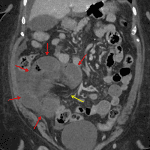

- Displaced loop of small bowel in the right lower quadrant with mild distension (measuring up to 3.5 cm in diameter) and mural thickening and hypoenhancement

- Two transition points are noted involving the afferent and efferent bowel segments, which are in close proximity to each other

- Additional mildly dilated loops of small bowel in the left lower quadrant without mural hypoenhancement or defined transition point

- Surgical changes of Roux-en-Y gastric bypass

- Small to moderate volume free intraperitoneal fluid, including right lower quadrant interloop fluid, without loculated collection or free air

- Closed-loop small bowel obstruction

Findings concerning for closed-loop small bowel obstruction in the right lower quadrant, likely related to an internal hernia in the setting of prior Roux-en-Y gastric bypass. No pneumatosis, portal venous gas, or pneumoperitoneum.